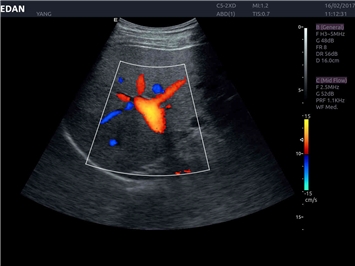

EDAN Acclarix LX4 представляет собой инновационную ультразвуковую систему, построенную на усовершенствованной платформе Acclarix. Сочетание высокого качества визуализации с интеллектуальным рабочим процессом делает эту систему оптимальным выбором для клиник, ценящих эффективность и экономичность.

• Акушерства и гинекологии

• Кардиологических исследований

Трехмерная реконструкция ЦДК:

Да